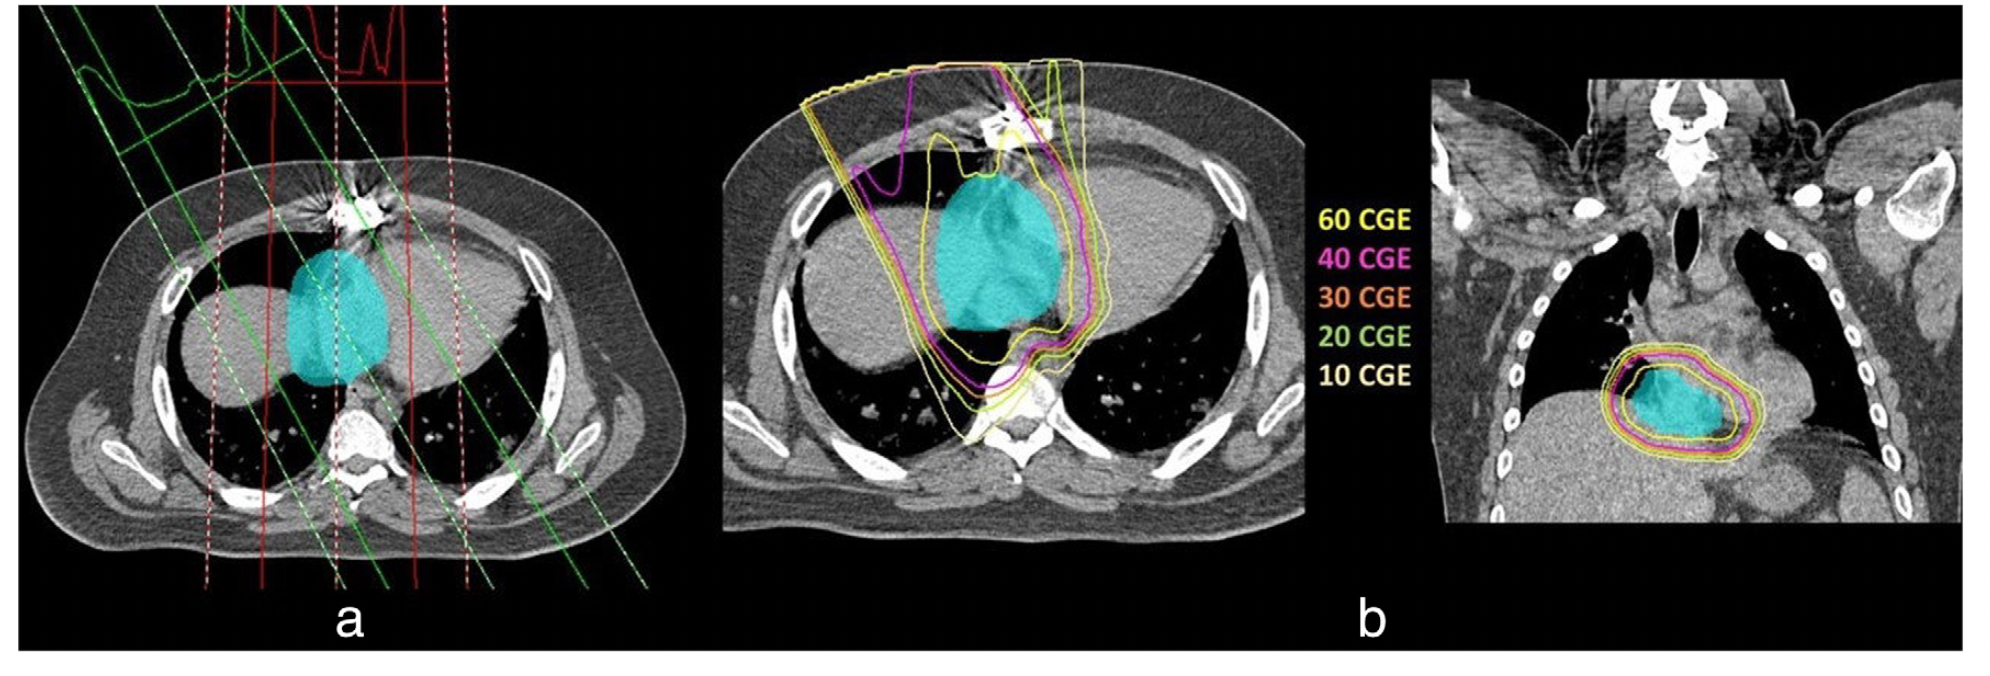

患者接受紧急手术切除,病理示上皮样血管肉瘤。免疫过氧化物酶染色显示肿瘤细胞CD31、CD34、ERG阳性,D2-440、HHV-8、细胞角蛋白AE1/AE3阴性。肿瘤大小10.5×6×4cmin,镜下见阳性边缘(R1切除)。术后两周行PET-CT扫描未发现任何远处转移。单纯切除以获得阴性切缘是不可行的,患者接受PBT联合紫杉醇治疗(每周80 mg/m2,共7个周期)。PBT的计划包括获得一个有或没有静脉造影剂的四维(4-D)CT模拟。心脏MRI检查后确定了具有临床目标量(CTV)风险的区域。 根据来自4-D CT模拟的图像,内部目标体积(ITV)为5毫米,用于扩展CTV以进行质子计划(图2)。

图2:(a)带内靶体积(ITV)靶的两场质子平面的波束定向。(b)淡蓝色洗涤的代表性等剂量线和ITV靶体积

患者在Mevion S250上采用双场质子计划,采用被动散射光束。与每周紫杉醇同时给予6120钴灰当量(CGE)的剂量,每天1.8CGE。在完成同步化疗和PBT后,使用吉西他滨(第1天和第8天900 mg/m2)和多西他赛(第8天100 mg/m2)进行全身化疗。三个周期后,发展为3级皮炎,导致停止治疗。由于再次CT扫描没有任何肿瘤复发,进一步的治疗被拒绝。治疗结束后18个月和手术后26个月,患者仍然处于完全释放状态。